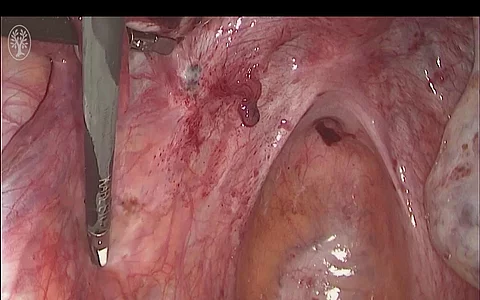

- Laparoskopie

- Laparotomie